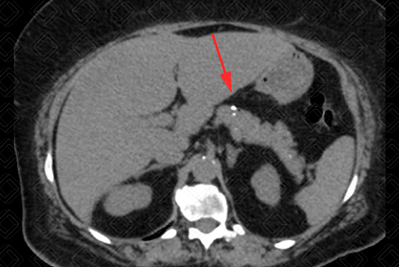

Texto alternativo para a imagem Figura 1. Créditos: Dra. Elazir Mota - Rio de Janeiro/RJ

Descrição das figuras 1 e 2: Tomografia computadorizada do abdome. Pâncreas com discreto afilamento difuso e apresentando focos de calcificação dispersos pelo parênquima pancreático (setas vermelhas).

• Tomografia computadorizada do abdome: Ducto pancreático principal dilatado (valor de referência normal até 3,5 mm), calcificações pancreáticas, redução do volume pancreático, alteração do seu contorno e surgimento de pseudocistos (figura 1);